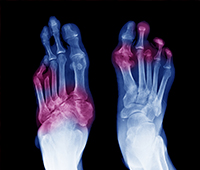

3. I am a diabetes patient and I have developed a foot infection. How can Ayurveda help me manage this better?

Foot infections are very common in people with diabetes as high blood sugar levels reduce the blood supply to legs, making them more prone to all kinds of foot problems. If you do not take timely care of your foot, it could lead to serious complications and even amputation.

Ayurveda can help you manage your foot infections with a special treatment called shodhana therapy. This therapy purifies the body and expels the aggravated doshas from the body. It includes five procedures or panchakarma indicated for different types of doshas.